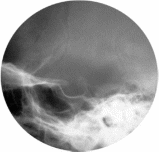

Рентгенологические исследования. Для диагностики патологии гипофиза долгие годы применялась рентгенография черепа в прямой и боковой проекциях, прицельная рентгенограмма, томограмма, на которых изучалось состояние турецкого седла, которое является костным ложем гипофиза. На рентгенограммах оценивают форму седла, состояние передней стенки, дна и спинки, сагиттальный и вертикальный размеры. Размеры и форма турецкого седла вариабельны.

Рисунок Рентгенограмма черепа в боковой проекции (стрелка – турецкое седло), прицельная рентгенограмма турецкого седла

Рентгенологическими признаками аденомы гипофиза являются изменение формы и размеров турецкого седла, истончение и деструкция костных структур, образующих его.

Рисунок Прицельная рентгенограмма турецкого седла. Макроаденома гипофиза. Увеличение размеров турецкого седла (стрелки) и разрушение нижней стенки.